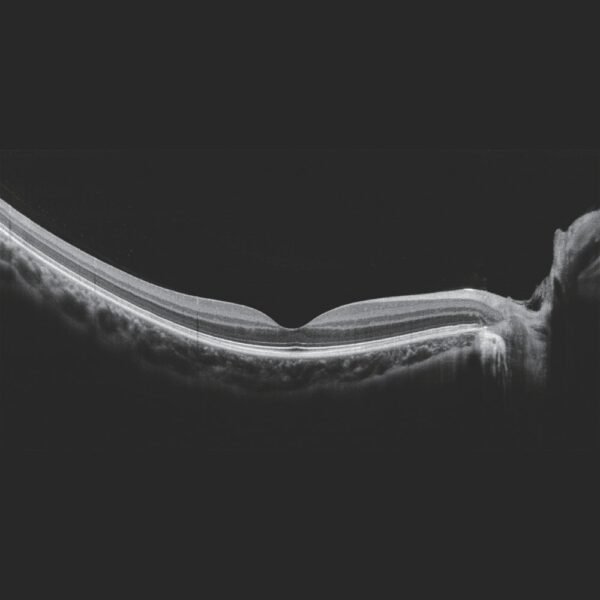

SLO-OCT e OCTA com VASCAN ADVANCE

O Mocean 4000 é configurado com os sistemas de imagens combinados SLO-OCT de ponta e o rastreador ocular baseado em SLO, uma plataforma poderosa para aplicações avançadas, como a angiografia OCT.